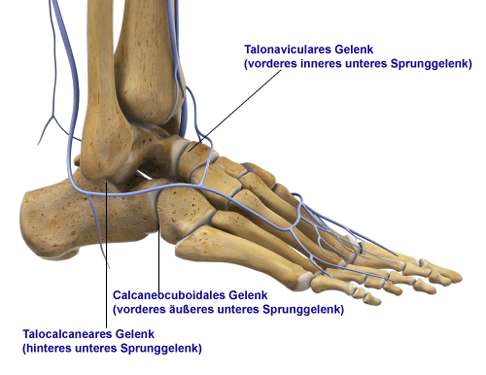

Wird aus Fersenbein, Sprungbein, Kahnbein und Würfelbein gebildet. - Arthrodese (Versteifung):

Setzt sich zusammen aus dem Gelenk zwischen Sprungbein und Kahnbein (talonaviculares Gelenk) und dem Gelenk zwischen Fersenbein und Würfelbein (calcaneocuboidales Gelenk).

Bei einer Triple-Arthrodese werden alle drei Anteile des unteren Sprunggelenks versteift, also alle Fußgelenke, die mit dem Sprungbein verbunden sind. Dazu zählen das zwischen dem Sprungbein und dem Fersenbein liegende talocalcaneare Gelenk (TCG oder Subtalargelenk) und die beiden vor dem Sprungbein liegenden Gelenke: das Sprungbein-Kahnbein-Gelenk (talonaviculares Gelenk, TNG) und das Fersenbein-Würfelbein-Gelenk (calcaneocuboidales Gelenk, CCG), welche gemeinsam das sog. Chopart-Gelenk bilden.